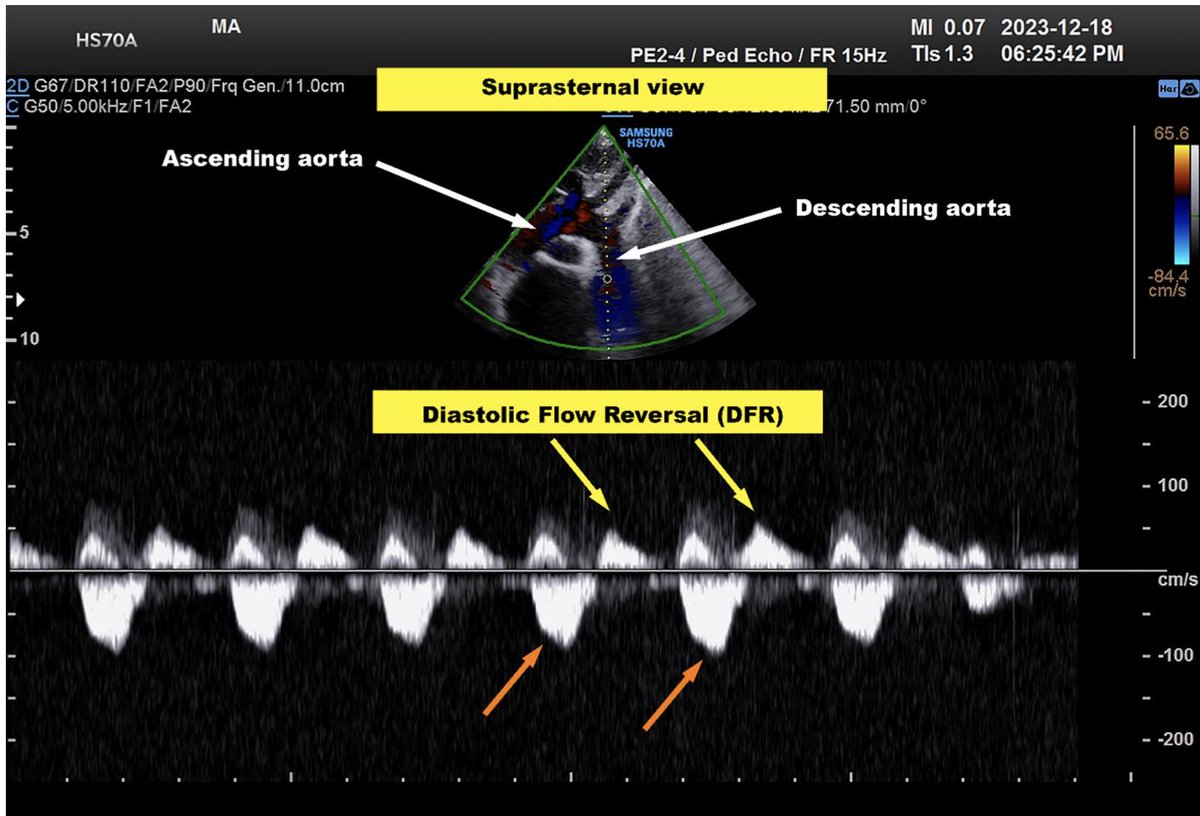

1. pmVSD jet beneath the RCC-NCC produces a Venturi effect —> secondary AR (Laubry–Pezzi Sd) 2. BAV morphology facilitates the development @WGACHDChair @loomba_rohit @iamritu @CASivaram1 @echoleolopez @dkthekkoott @AEPCcongenital @alexsfelixecho @alex1708ander @DavidWienerMD